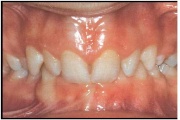

Valehambumus

Hammaste asendianomaaliad on tingitud tavaliselt arenguhäirest.

Sümptomid:

(18)